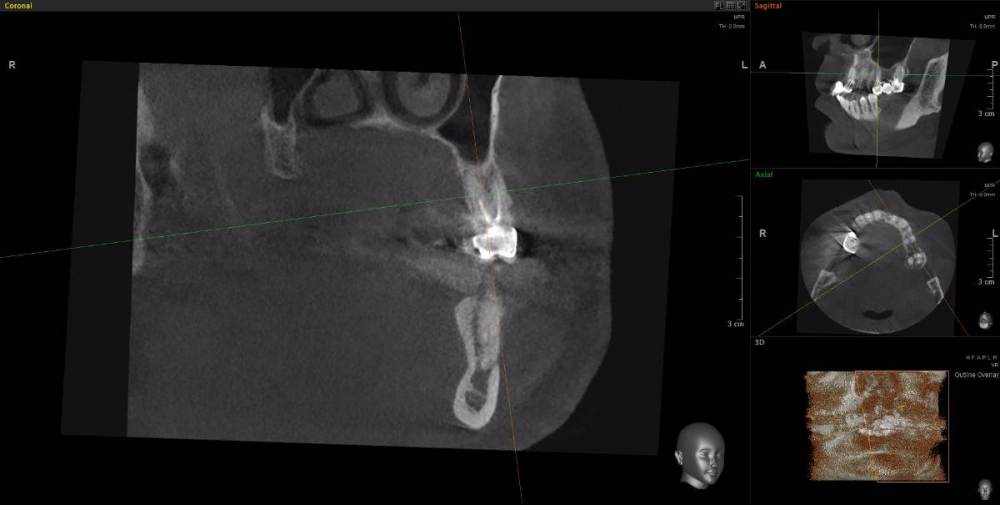

Dude Опубликовано 1 апреля, 2021 Поделиться Опубликовано 1 апреля, 2021 По плану в 1 этапе, кроме остального: лечение каналов и укрепление их стекловолоконными штифтами: 16, 25, 27, 44, 47; имплантация 14, 15, 17, 12, 11, 21, 22, 24, 26, 36, 37, 46, 45. Во 2 этапе (через 5-6 месяцев) установка коронок. Лечение в другой стране. Чтобы сократить длительность первого этапа, предложили лечение зубов сделать на 2 этапе. Очень засомневался, можно делать имплантацию с невылеченными зубами? Ссылка на комментарий

Dude Опубликовано 1 апреля, 2021 Автор Поделиться Опубликовано 1 апреля, 2021 https://disk.yandex.ru/d/6d0pmZ1zArn1Og Так? Ссылка на комментарий

wladdX Опубликовано 1 апреля, 2021 Поделиться Опубликовано 1 апреля, 2021 Я бы повторное лечение к\каналов рекомендовал провести до хирургии. Конечно, может быть и другое мнение. Скрытый текст 1 Ссылка на комментарий